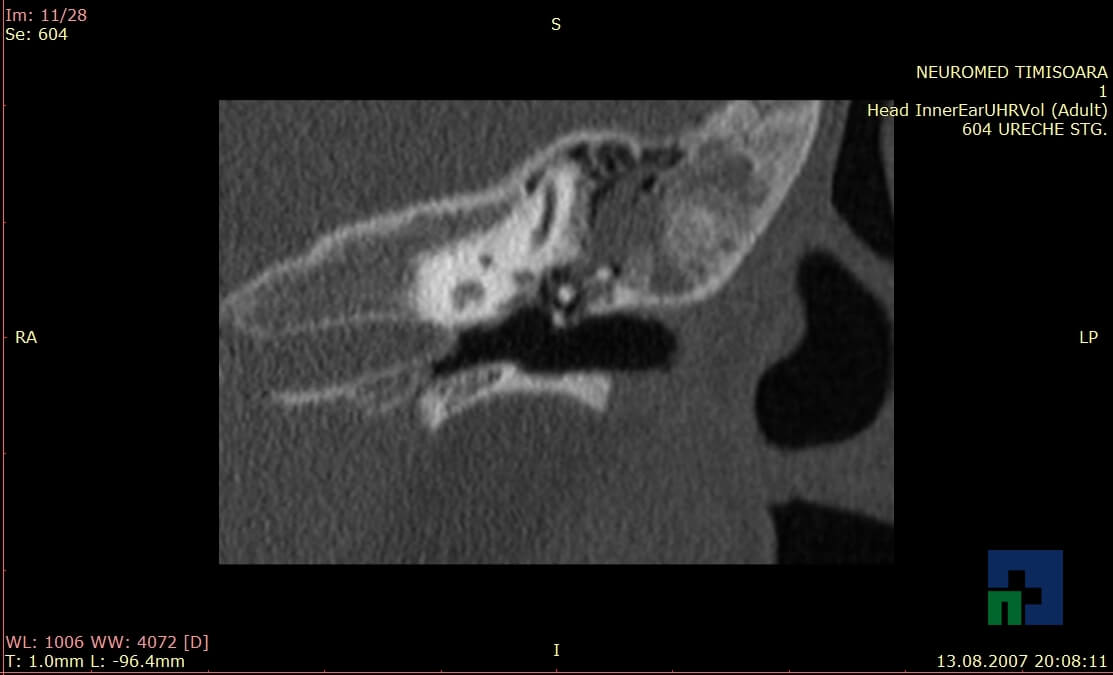

- Diagnosticul traumatismelor de bază de craniu

- Diagnosticul fracturilor: